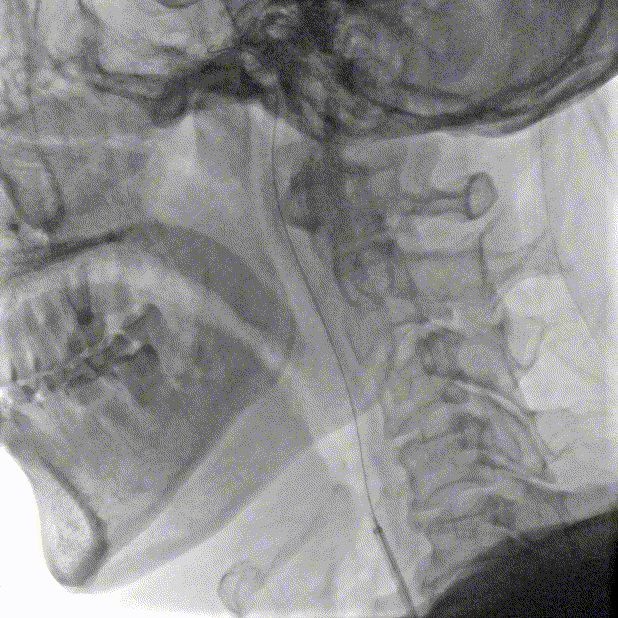

主动脉弓上血管多发斑块形成。

左侧锁骨下动脉显示左侧椎动脉开口重度狭窄,狭窄率85%,供血至PICA。

双侧颈动脉造影提示双侧颈内动脉多发斑块形成,远端血管显影良好。

右侧锁骨下动脉造影提示右侧椎动脉主供血,开口无狭窄,椎动脉V4段局限性重度狭窄,狭窄率 80%,远端基底动脉及分支血管显影良好。

常规消毒、铺巾后,采用改良Seldinger技术穿刺右桡动脉。造影导丝和Sim2造影导管将7F EasyRadial™输送导管置于椎动脉。

正侧位造影提示右侧椎动脉重度狭窄。

200cm微导丝携带微导管路图下穿过狭窄段至左侧大脑后动脉P2段。

沿微导丝送入3.0*15mm 颅内球囊扩张导管至狭窄段给予球囊扩张术。

造影证实狭窄较前明显改善。

撤出颅内球囊扩张导管。

沿微导丝送入3.0*12mm 颅内药物洗脱支架至狭窄段。

准确定位后给予球囊扩张、释放支架。

术后造影造影证实支架打开良好,贴壁良好,无残余狭窄,远端未见明显栓塞表现。